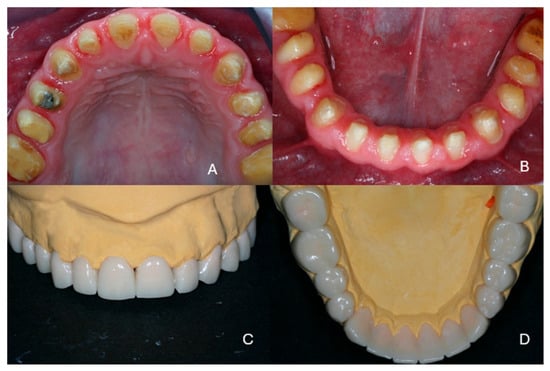

2. Case Presentation